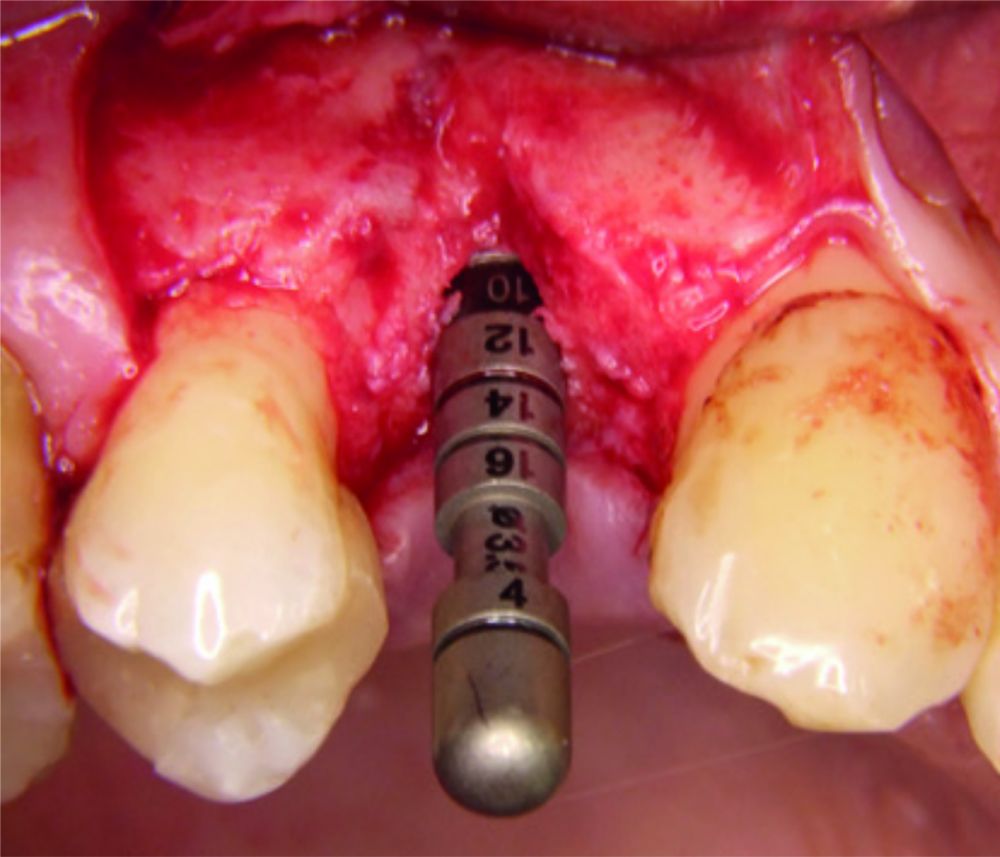

| Adjuvante nicht-chirurgische Behandlung von Periimplant-Mukositis oder Periimplantitis |

|

Adjuvante Behandlung einer persistierenden

entzündeten Zahntasche

Prof. Dr. Stefan Fickl

Deutschland